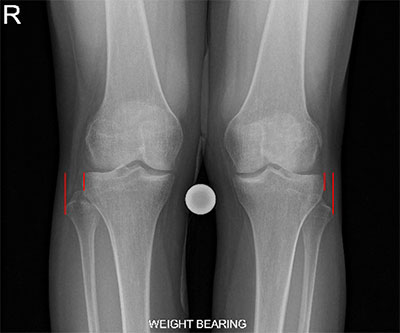

- Lateral and AP x-rays of the knee are often taken. On the lateral x-ray, the fibular head should be behind the posteromedial portion of the lateral tibial condyle known as the Resnick’s line. Displacement of the fibular head will disrupt this relationship. There are variable degrees of knee rotation on the lateral x-ray so an x-ray with 45-60 degrees of internal rotation is preferable for the PTFJ [5]. On the AP radiograph, half of the fibula head should be behind the lateral margin of the lateral tibial condyle. In an anterolateral dislocation the fibula will have less than half of its head overlapped. Axial computed tomography is the most accurate imaging to detect a proximal tibiofibular joint injury. Subtle proximal dislocations can be missed so comparison with the contralateral knee may improve detection.